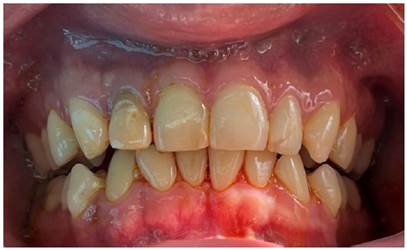

Paciente masculino de 24 años de edad, sin antecedentes patológicos de relevancia, acude a consulta privada indicando que le detectaron un quiste en maxilar superior sectante anterior, mediante control radiográfico en 2019. No presenta sintomatología al momento de la evaluación clínica, al examen intraoral se observa discromía en pieza 1,2 y obturación provisional por palatino (Figura 1).